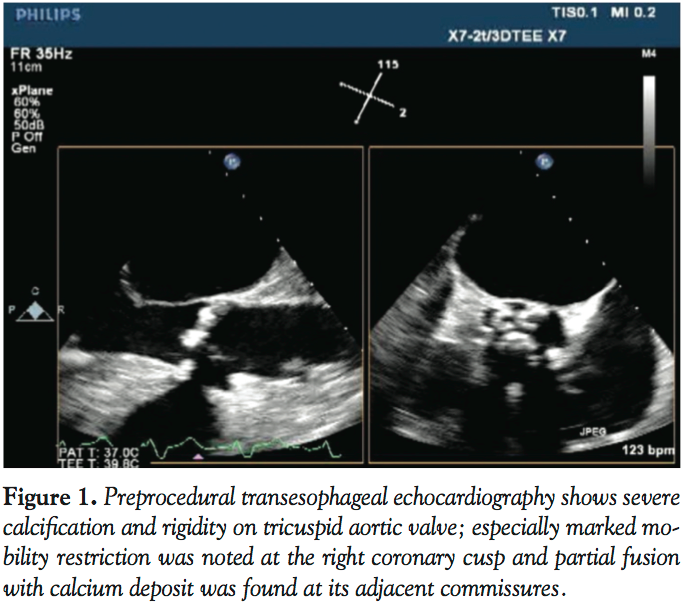

A 73-year-old man was admitted to our hospital with dyspnea. He was diagnosed with congestive heart failure due to severe aortic stenosis. Despite full inotropic and mechanical ventilator support, his condition did not improve and remained Forrester class IV. To improve hemodynamics, PTAV was performed via a retrograde femoral artery approach under mechanical ventilation support and tranesophageal echocardiography (TEE) guidance. TEE showed a severely stenotic tricuspid aortic valve with calcification of each leaflet

and commissure (Figure 1). Markedly reduced mobility was found at the right coronary cusp due to its extensive calcification and calcified stiffness of the adjacent commissures. Aortic annulus diameter was measured as 20.5 mm by TEE. Simultaneous aortic and left ventricular pressures before valvuloplasty showed peak and mean pressure gradient of 82.6 and 57.7 mm Hg, respectively, and aortic valve area (AVA) was calculated as 0.64 cm2 (Figure 2A). Following two 20 mm balloon inflations (Z-MED II; NuMED), peak and